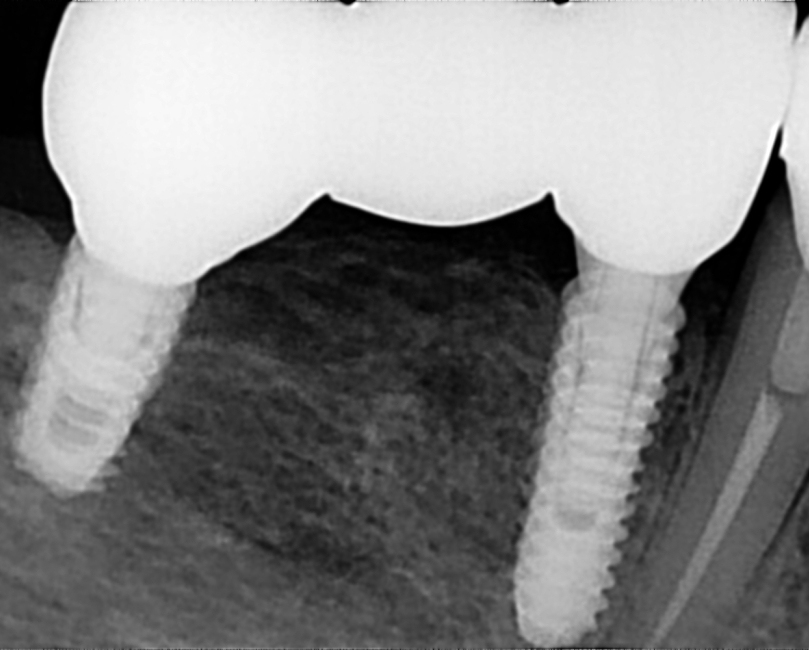

Terapija obuhvaća različite kirurške zahvate, uključujući vađenje zuba, apikotomiju i ugradnju implantata. U našem centru koristimo suvremene tehnike i materijale, pružajući svakom pacijentu personaliziranu i stručnu njegu, s naglaskom na minimalnu invazivnost i maksimalnu preciznost.